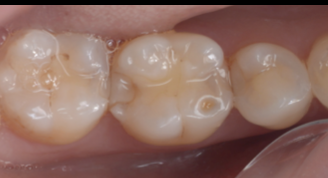

【40代 女性】

詰め物が劣化した

- 担当医

- 生野 誠

- 主訴

- 詰め物が劣化した

虫歯になってないか不安

- 期間

- 1回

- 費用

- 7万

- 治療内容

- ダイレクトボンディング

- 治療に伴うリスク

- コンポジットレジンの劣化